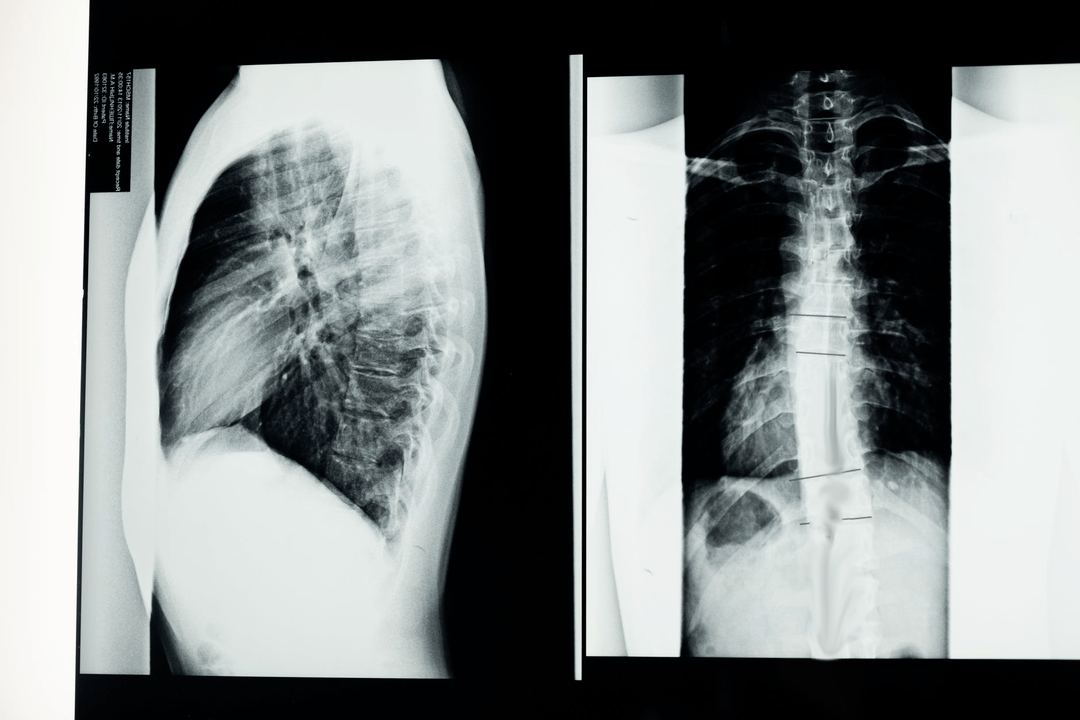

Преди да започне диагностични изследвания, неврологът събира медицинската история на пациента и внимателно изучава оплакванията му. Остеохондрозата има общи симптоми с някои други заболявания, така че е важно да можете да разграничите патологиите. Рентгеновите изследвания ще помогнат да се потвърди диагнозата остеохондроза: радиография, миелография и компютърна томография.

Проучвателната рентгенова снимка ви позволява да получите рентгеново изображение на гръбначния стълб или част от него. По този начин лекарят може да определи мястото, засегнато от заболяването. За по-голяма яснота ще обясним как остеохондрозата може да се определи чрез рентгенова снимка: изображението ще покаже стесняване на междупрешленния диск, наличие на костни израстъци (остеофити) или промяна във формата на гръбначния сегмент.